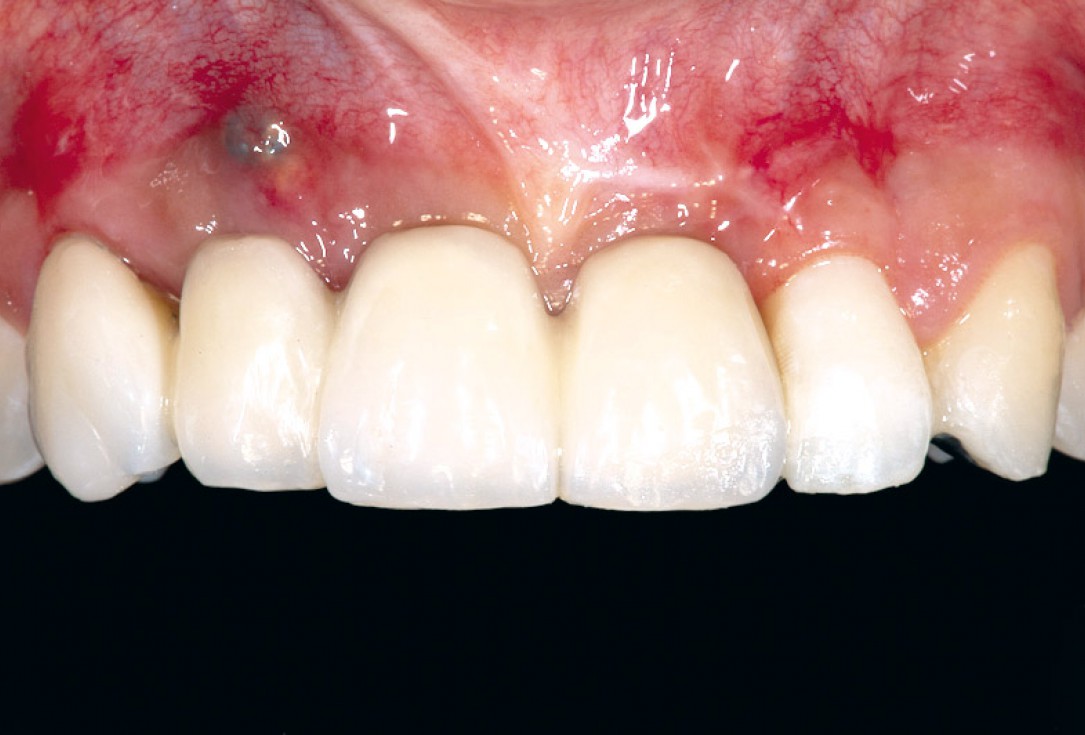

15/17 - Situation after sutures removal and healing period of two weeks